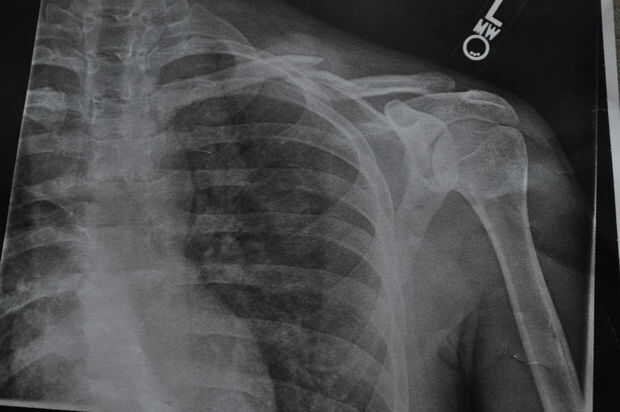

Tengo un accidente de bicicleta recientemente y había dañado mi bicicleta motorizada. Lo que sucedió fue que en la noche y pulsó una isla sin marcar camino (que era de nueva construcción). Estaba tirado de la moto y aterrizó en mi hombro izquierdo rompiendo mi clavícula. Fui corriendo al hospital y rayos x hace que nada se rompió. Afortunadamente yo llevaba un casco de otra manera habría tenido un cráneo agrietado y una conmoción cerebral severa. POR FAVOR! Usar un casco al montar en cualquier tipo de bicicleta me salvó la vida.